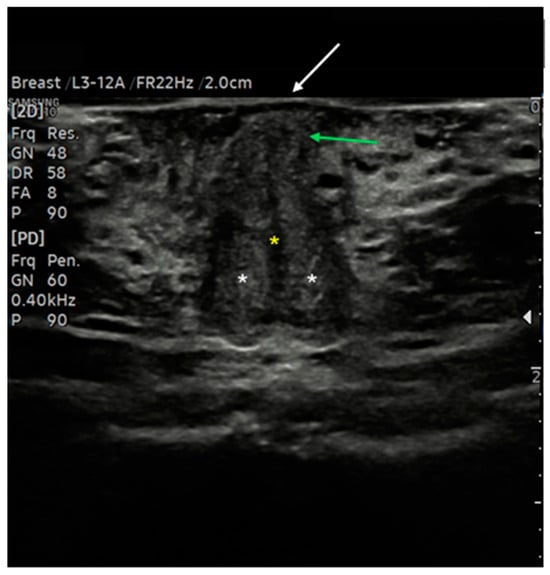

7.2. Vulvar Dermatosis and Precancerous Lesions